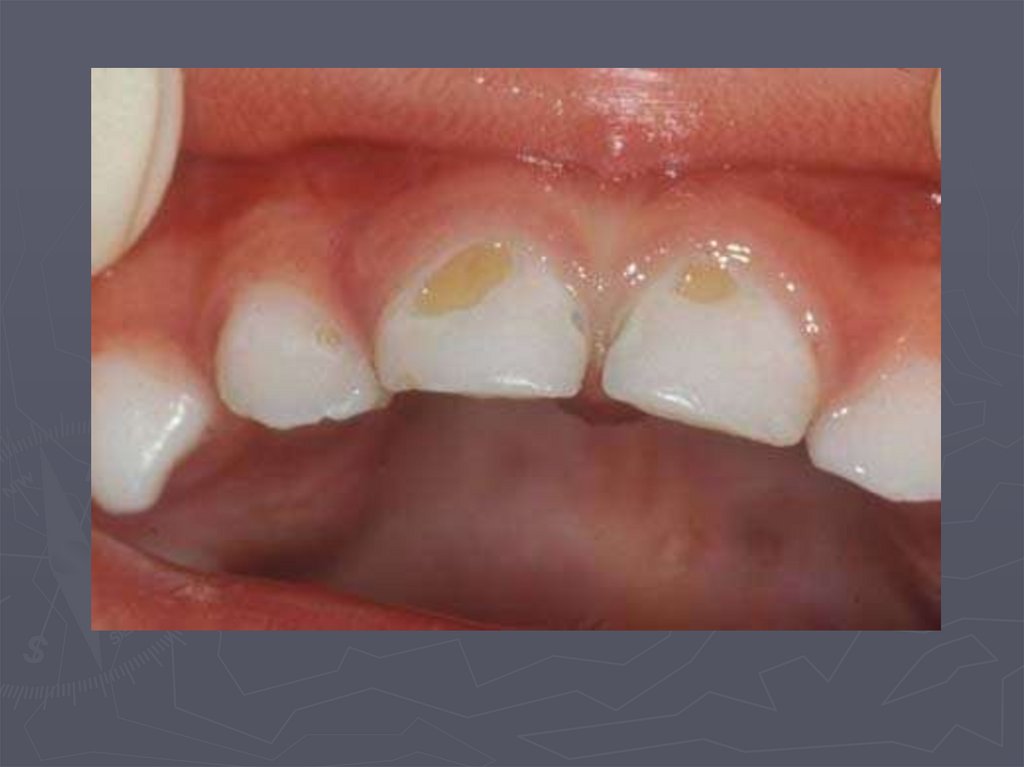

4. ОСОБЕННОСТИ КЛИНИЧЕСКОГО ПРОЯВЛЕНИЯ КАРИЕСА У ДЕТЕЙ РАННЕГО ВОЗРАСТА

У детей в возрасте от 1года до 3 лет КАРИЕС

чаще возникает:

► на зубах, имеющих порочно развитые ткани в виде

гипоплазии;

► ткани этих зубов недостаточно минерализованы;

► чаще поражаются резцы;

► затем моляры и клыки;

► преимущественная локализация кариозной полости на

вестибулярной и контактной поверхности резцов ;

► а также в фиссурах моляров;

► нередко кариес начинается в пришеечной области;

► процесс распространяется вокруг всей коронки;

► формируется циркулярный кариес.